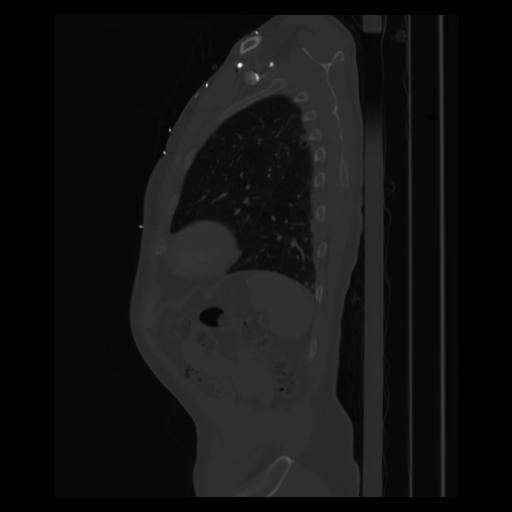

30 CUERPO,CE,Sagittal,3.000,CUERPO,Sagittal,